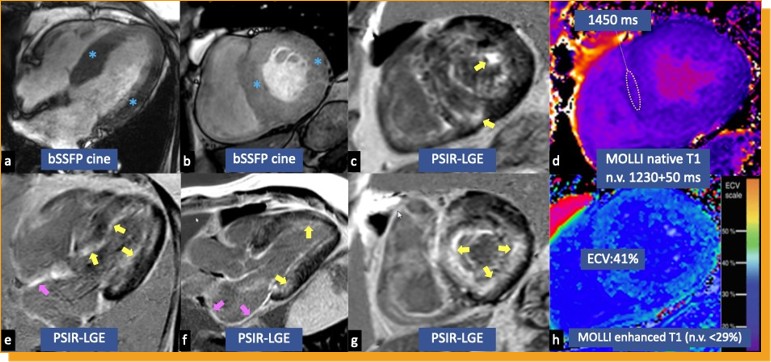

ECO4

- Fenotipo hipertrófico con rasgos infiltrativos

- Llenado restrictivo del VI con engrosamiento de la pared del VD

- Bajo e′ septal o lateral

- Disminución del strain longitudinal global